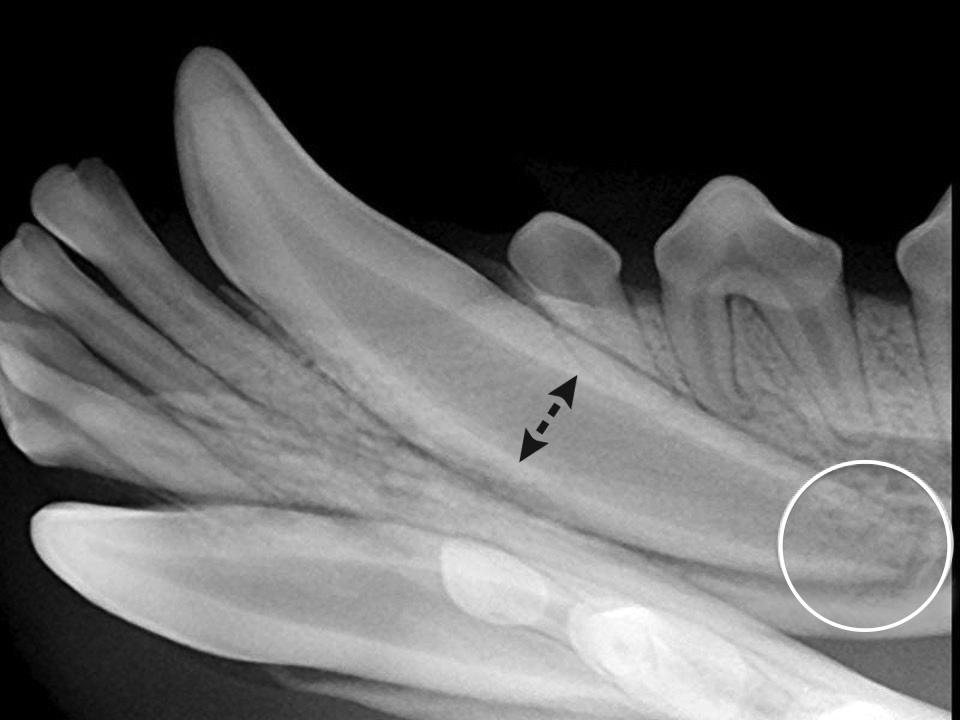

Dental Radiography Taking the Xrays OSU CVM Veterinary Clinical

Interpreting Dental Radiographs Clinician's Brief Dental Radiographs Practice radiographic imaging is an integral part of the diagnostic process in clinical dentistry. the american dental association (ada) has various policies and recommendations to help dentists ensure that patients’. the european academy of paediatric dentistry (eapd) proposes this best clinical practice guidance to help. quiz yourself with questions and answers for dental radiology practice test, so. Dental Radiographs Practice.

How to Interpret Dental Radiographs Clinician's Brief Dental Radiographs Practice This article provides the fundamentals of. the european academy of paediatric dentistry (eapd) proposes this best clinical practice guidance to help. the american dental association (ada) has various policies and recommendations to help dentists ensure that patients’. radiographic imaging is an integral part of the diagnostic process in clinical dentistry. quiz yourself with questions and answers. Dental Radiographs Practice.